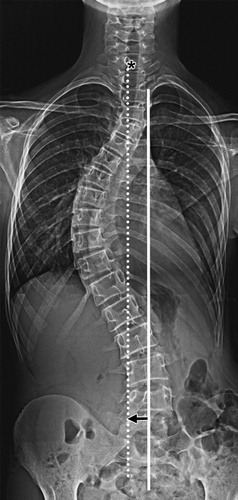

وبصفة عامة فإن الانحناءات التي تتراوح بين ال25 و ال50 درجة يتم اعتبارها كبيرة إلى حد ما بحيث تحتاج إلى العلاج. وبالنسبة للانحناءات التي تزيد عن 50 درجة فسوف تحتاج إلى الجراحة للحصول على الشكل السليم للوضعية

يطرح الطبيب المعالج خيار الجراحة عندما تكون درجة الانحناء أكثر من 45 درجة في مرحلة النمو او اكبر من 50 درجة في مرحلة ما بعد النمو